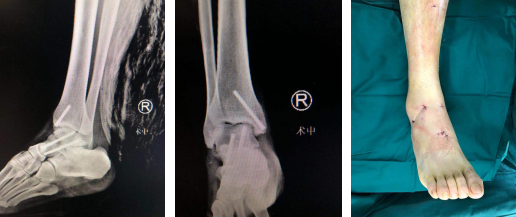

术后(左/中图)创口微乎其微,患者非常满意(右图)